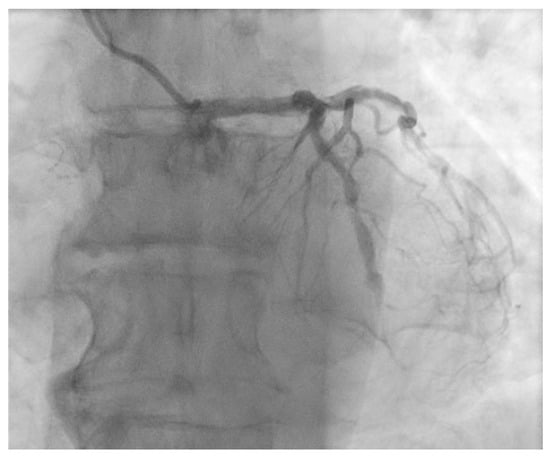

2. Case Presentation